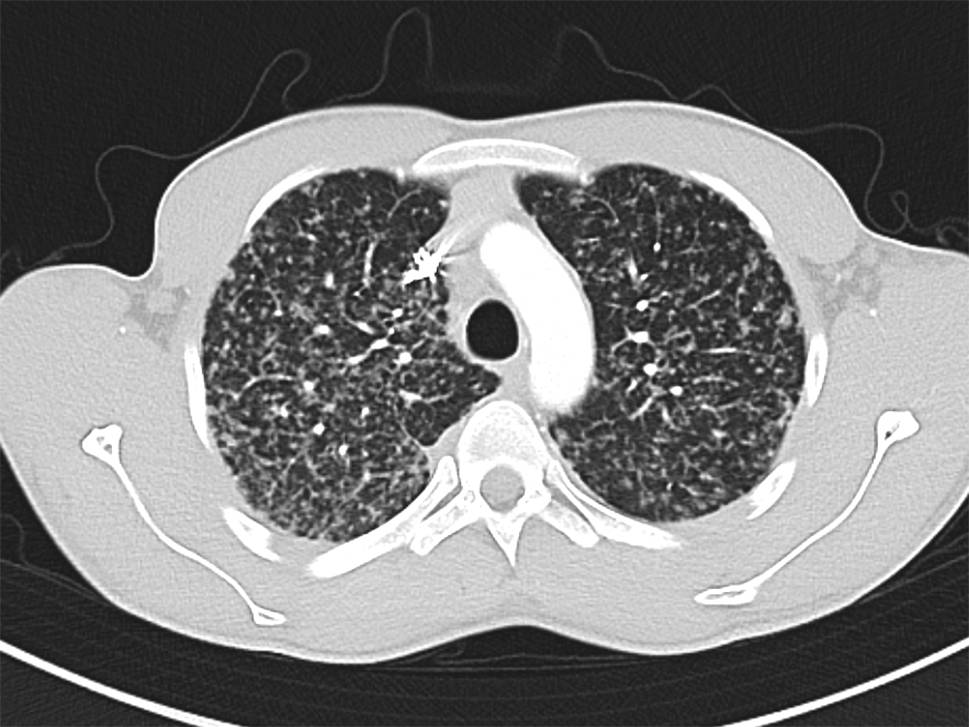

Die Computertomographie (CT) des Thorax ist ein wesentlich präziseres diagnostisches Werkzeug, welches eine detaillierte Darstellung granulomatöser Manifestationen sowie lymphatischer Involvierung intra- und extrathorakal ermöglicht (Abb. 2 und 3).

Abb. 3

CT-morphologisches Bild einer SAPF mit bronchozentrischer Betonung, Bildung von Traktionsbronchiektasen und Volumsreduktion. (Quelle: KUK Linz, Universitätsklinik für Innere Medizin 4 – Pneumologie)

In der CT werden Lungenparenchymveränderungen bei Sarkoidose in nichtfibrotische und fibrotische Veränderungen unterteilt, wobei nichtfibrotische Lungenparenchymveränderungen sich als multiple peribronchovaskuläre, perifissurale oder subpleurale Mikronoduli, als multiple größere peribronchovaskuläre Noduli, als verstreute größere Knötchen oder als Konsolidierung als die vorherrschende oder einzige Anomalie manifestieren [17]. Eine Lungenfibrose bei Sarkoidose kann sich mit bronchozentrischen Retikulationen mit oder ohne dichte parenchymale Konsolidierungen, mit oder ohne Kavernenbildung oder als große bronchozentrische Konsolidierungen manifestieren [17]. Vor allem eine bihiläre Lymphadenopathie in Kombination mit mikronodulären Parenchymveränderungen mit perilymphatischer Anordnung (Beteiligung der Pleura und der Fissuren) ist bei entsprechendem klinischem Kontext hochgradig suggestiv für die pulmonale Sarkoidose [18].